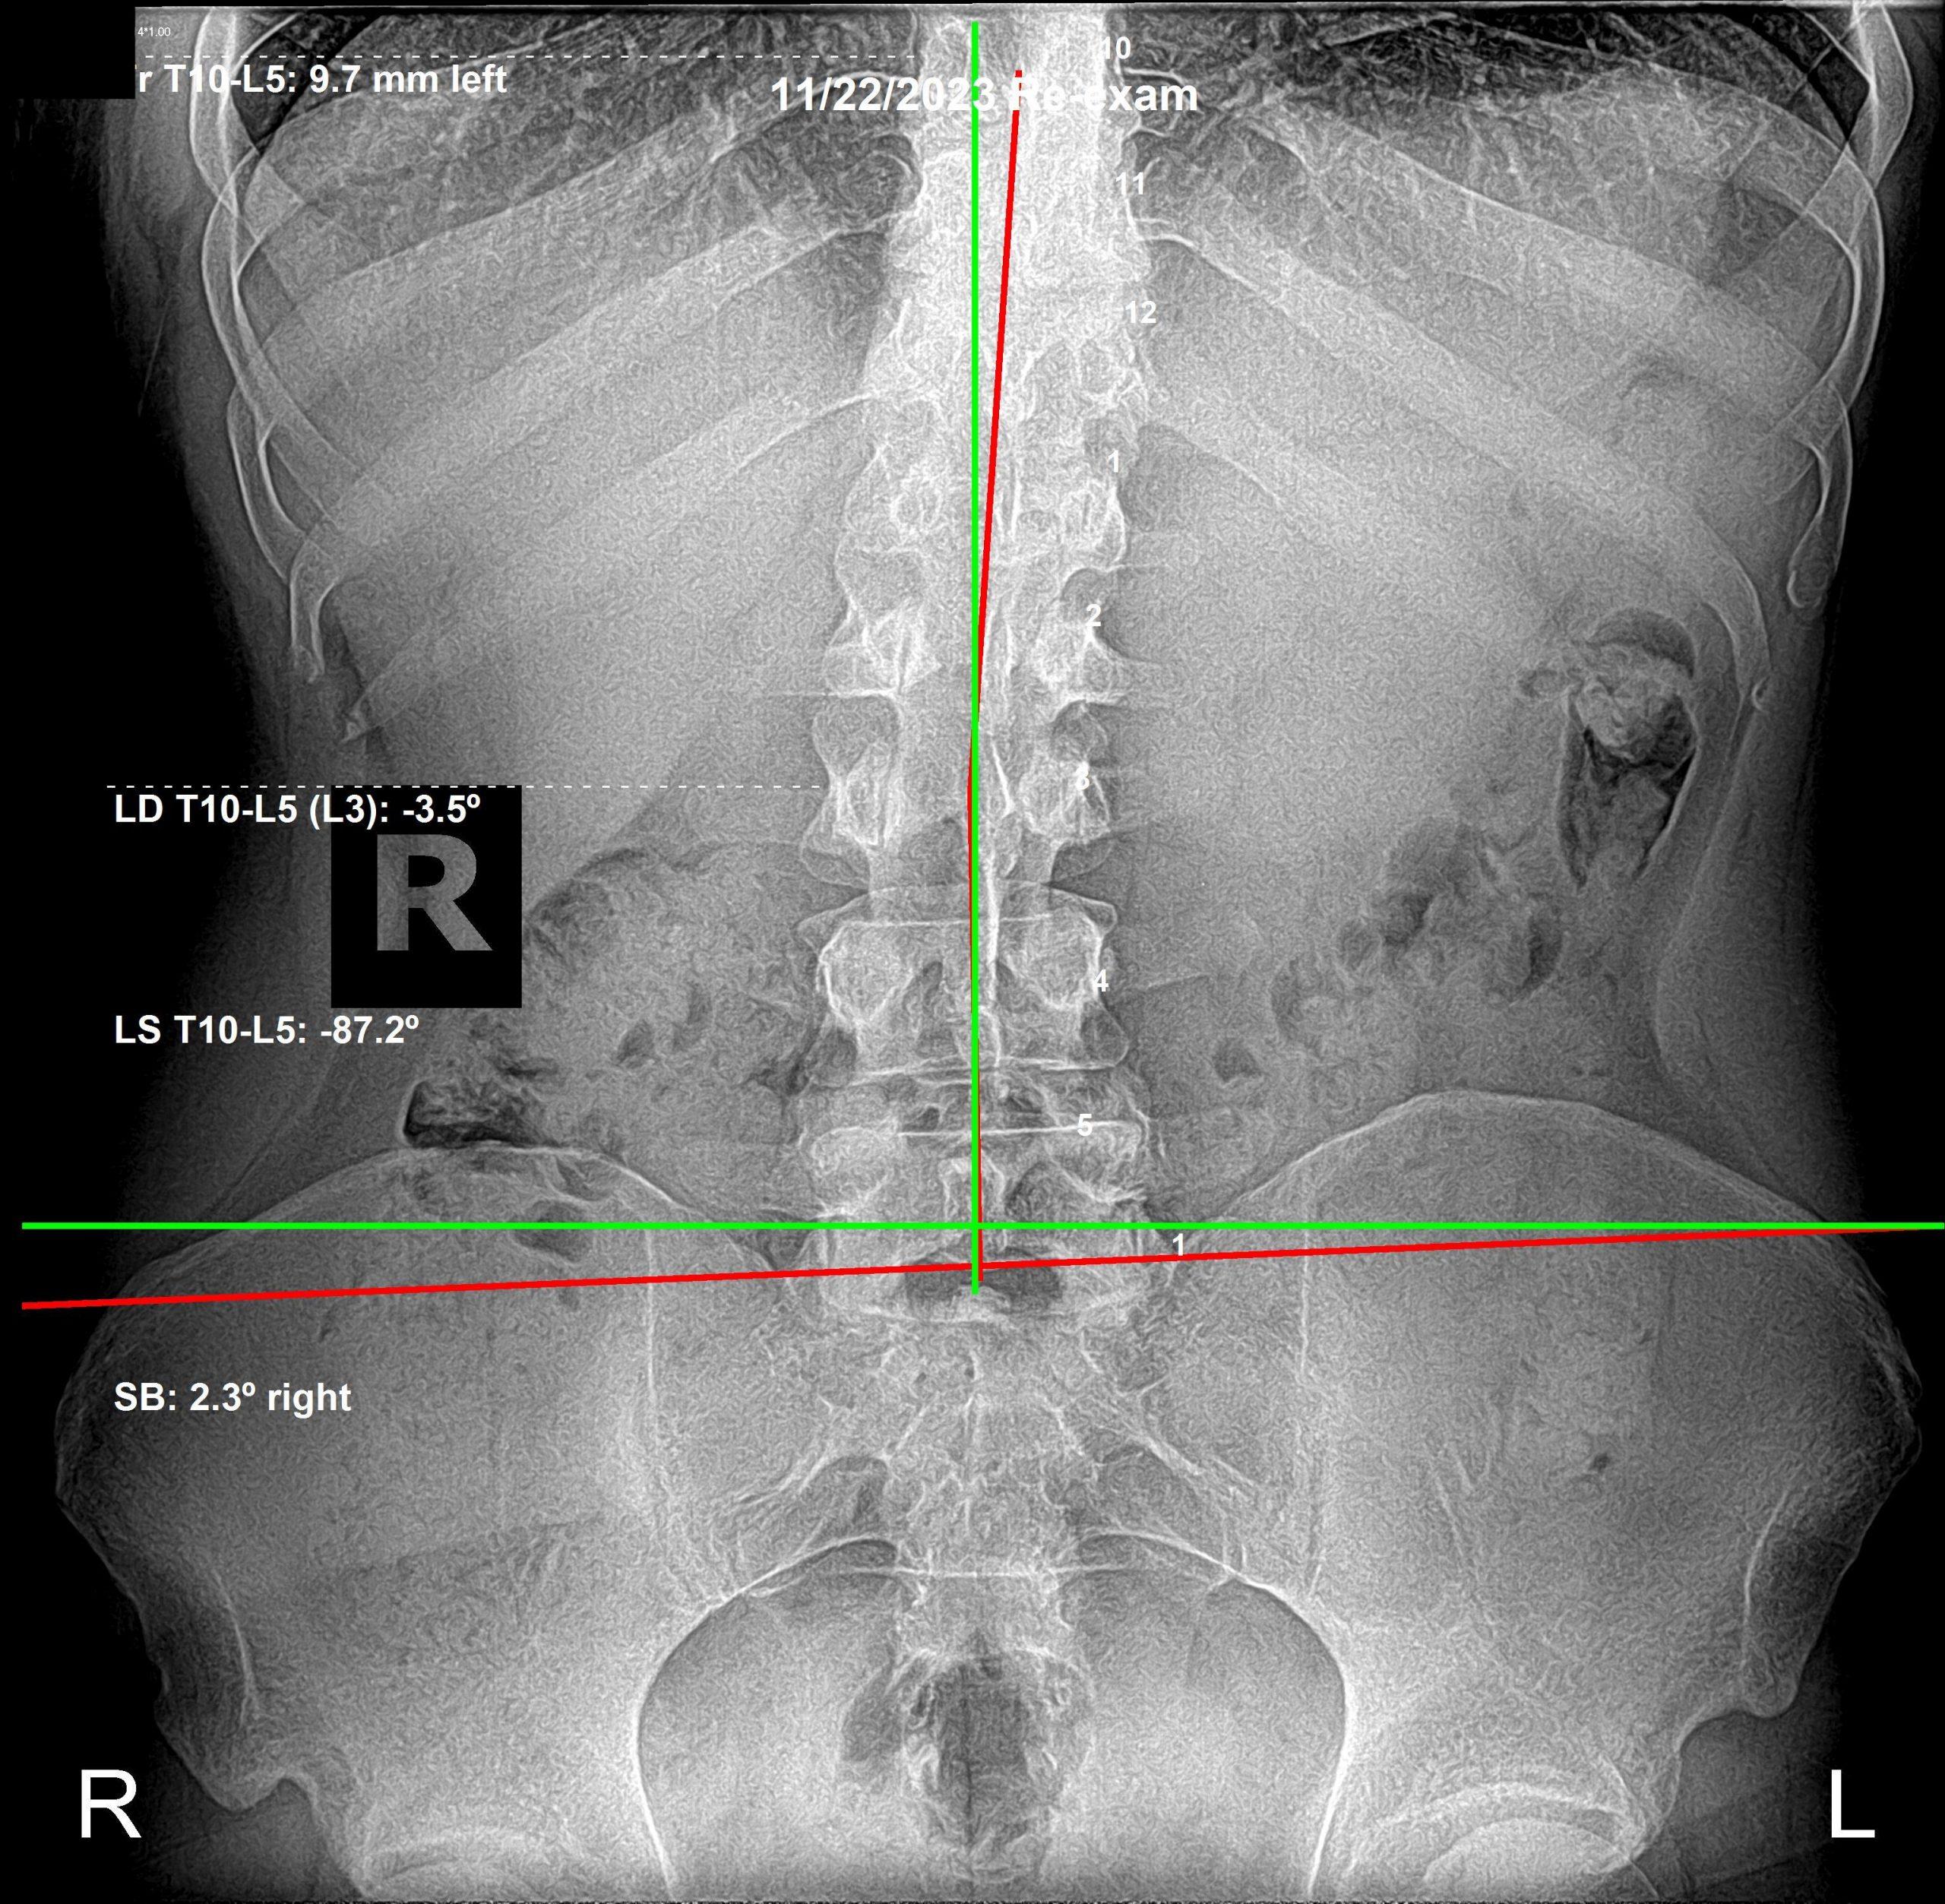

And then a series of high-stress life events occurred. He began having low back pain (which he had never complained of before), his upper back posture appeared to be worsening, and he started experiencing ankle pain and discomfort.

AP lumbar X-ray after chiropractic care

AP View — After Care

All of these new issues are related. We are kinetic chains — everything connected through motion. As his spine changed, specifically his pelvis, other areas appeared worse on film — even though functionally he was improving.